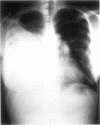

A case is presented of massive ascites and right sided pleural effusion caused by endometriosis. The final diagnosis was not made for a considerable time. Massive ascites and a right sided pleural effusion caused by endometriosis is rare, with fewer than 10 reports in the literature worldwide. Physicians should be aware of this potentially tentially treatable cause, having excluded other possibilities such as malignancy and tuberculosis.